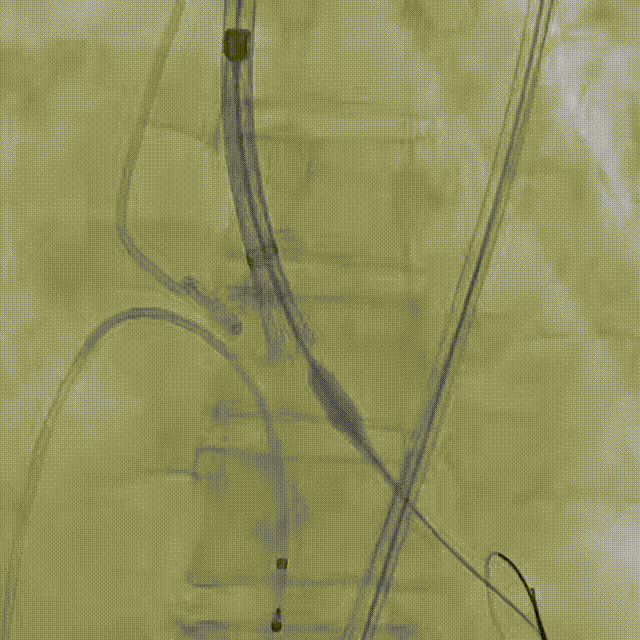

患者病史 主诉:发作性胸闷憋喘半年,加重伴呼吸困难2周。 现病史:患者半年前无明显诱因出现胸闷、憋喘,伴有下肢水肿,2周前上述症状明显加重,夜间不能平卧,痰中带血丝,为进一步诊治再次来我院,门诊以"心力衰竭"收入院。 既往史:肾功能不全、心房颤动 心脏超声提示:LVEF:0.54 1.主动脉瓣病变;2.主动脉瓣狭窄(重度)并反流(中度);3左室壁节段性运动不良;4.升主动脉扩张、双房扩大、左室肥厚;5.二尖瓣硬化并反流(中度);6.三尖瓣反流(轻-中度);7.肺动脉瓣反流;8.肺动脉高压(轻度)PGmean=105mmHg,Vmax=635cm/s,瓣口面积0.27cm²。 术前CT评估 Type0型二叶瓣,重度钙化,钙化集中在瓣叶游离缘,右冠窦为著;左冠高度11.8mm,由于左冠窦部空间较小,左冠风险较高, 升主动脉扩张,最宽处50.5mm;主动脉瓣环水平夹角61.5°,横位心。主动脉弓角77.6°,锐角弓,外周入路在腹主及髂总处有大量散状钙化,胸主处有81.6°的迂曲。 手术策略 推荐右侧股动脉为主入路,左侧股动脉为辅入路,送snare辅助过弯,使用18F大鞘,推荐预装ProStyle A® AV23瓣膜,20mm球囊预扩,初始定位对齐真实瓣环瓣上5mm超高位初始定位释放,释放过程中使瓣膜自然下滑,到工作位观察瓣膜形态,最终理想位置0-瓣下3mm。 手术过程 Step1:右侧股动脉为主入路、左侧股动脉为辅入路,成功穿刺并送入 18F 大鞘; Step2:主动脉根部造影,瓣口限制重 Step3:Type 0 型二叶瓣畸形合并重度钙化,患者瓣口狭窄严重,同时横位心,不仅导丝跨瓣困难,导管更难进入;术者凭借精湛操作,将导丝顺利跨瓣,反复微调导管角度,最终导管顺利过瓣。 导丝精准跨瓣 Step4:20mm球囊跨瓣困难,snare辅助下球囊成功跨瓣,预扩有腰无漏,冠脉充盈良好。 Step5: snare辅助下成功跨瓣,可以看到系统过弓形态瓣膜仓柔软,过弓顺滑 输送系统过弓 Step6:初始定位瓣上5mm开始释放,释放部分后观察瓣架下缘内收明显,后回收系统重新定位 初始定位 底部内收 Step7:瓣膜完全释放前,血压一度降低,术者迅速调整器械,实现瓣膜迅速锚定,快速释放 完全释放 Step8:20mm球囊后扩 最终造影,位置(瓣下3mm)形态良好 手术难点 患者不仅有主动脉瓣重度狭窄,还叠加肾功能不全、心房颤动等基础疾病,术中血流动力学波动极易引发心功能衰竭。ProStyle A® 预装干瓣“开包即用” 的特性压缩了术者操作时间,80%可回收设计给了术者容错空间,而这些看似难以逾越的难关,最终被团队精湛的医术一一化解,术中对于导丝、导管、球囊等器械每一步的精准操控,再到突发状况的从容处置,无不彰显着团队深厚的专业积淀与顶尖的操作技艺。 结语 此次手术的圆满成功,不仅彰显了陈玉国、李传保教授团队在复杂结构性心脏病介入治疗领域深厚的专业造诣与攻坚克难的决心,也充分验证了ProStyle A®系统在应对复杂高难度病例时的卓越适用性与有效性。 作为扎根齐鲁、享誉全国的医疗高地,山东大学齐鲁医院始终赓续着这片热土的仁厚文脉,将“医道从德,术业求精”的院训精神镌刻在每一次诊疗实践之中。特别是在结构性心脏病诊疗领域,医院团队始终怀揣医者担当,勇攀医学高峰,不断以更前沿的技术突破,为危重患者点亮重获新生的希望。 专家简介 陈玉国 山东大学齐鲁医院(点击查看专家详细简历) 李传保 山东大学齐鲁医院(点击查看专家详细简历) · END ·

根部造影